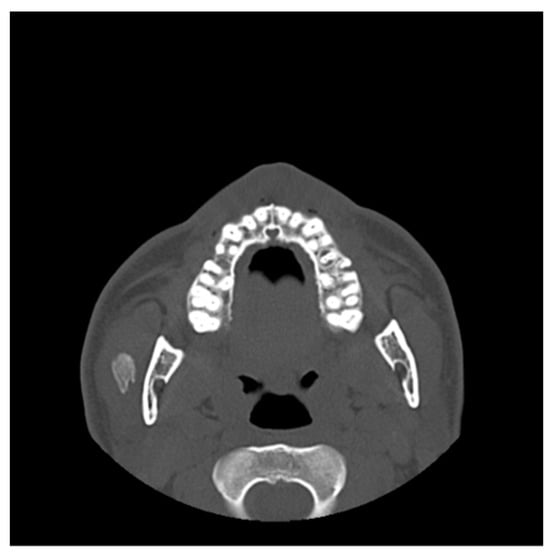

| 2 | Female | 10 | Bilateral hyperplasia of the coronoid processes |

OPG CT | 17 mm | Bilateral coronoidectomy | 45 mm |